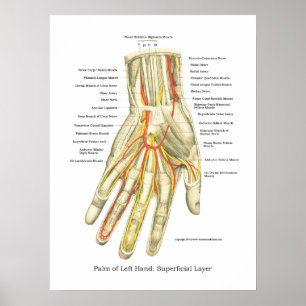

Poster interno da anatomia da mão & do pulso

Preço44,35 €